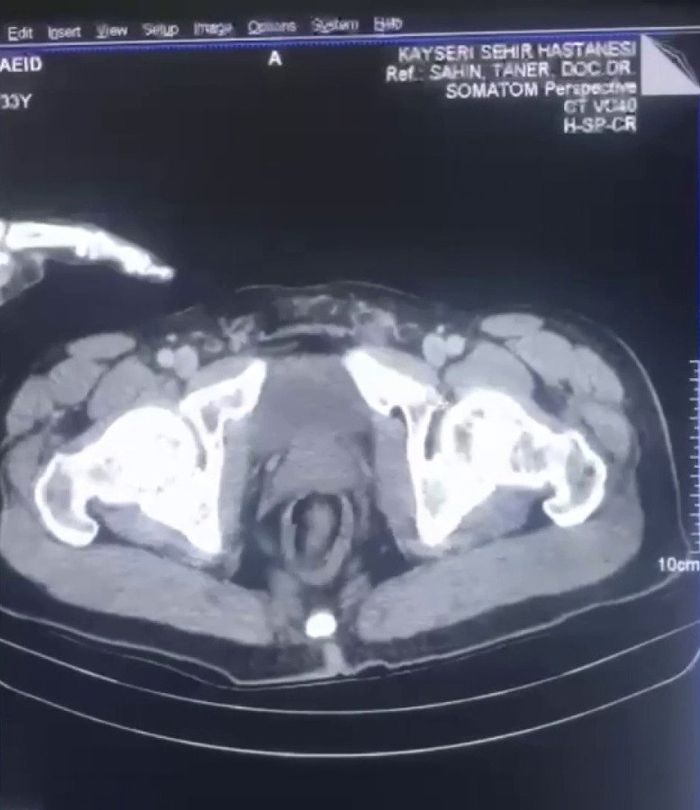

Üst aramasında uyuşturucu madde bulunamayan şüphelilerin, Kayseri Şehir Hastanesinde yapılan iç beden muayenesinde midelerinde 17 kapsül halinde 212,8 gram uyuşturucu madde olduğu tespit edildi.

AA'nın haberine göre; kapsüller, tıbbi yollarla şüphelilerin midesinden çıkarıldı.